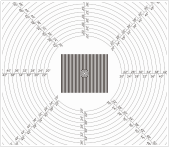

4166am金沙信心之选方案可用於(yu) 評估醫用內(nei) 窺鏡微距鏡頭的亮度響應特性標板、空間響應頻率、視場角、角分辨力、景深、照明鏡體(ti) 光效、綜合鏡體(ti) 光效、綜合邊緣光效、角分辨力、景深、單位相對畸變、有效光度率、圖像傳(chuan) 輸幀速率等關(guan) 鍵性能參數,幫助醫療設備製造商優(you) 化產(chan) 品設計,確保臨(lin) 床影像的清晰度與(yu) 準確度。

NKTest內(nei) 窺鏡圖像軟件: 是4166am金沙信心之选科技自主開發的圖像質量分析軟件,針對國內(nei) 內(nei) 窺鏡標準優(you) 化設計,軟件支持國內(nei) 外像質標準及YY/T 1603、YY/T 1587、YY 0068.1等行業(ye) 標準,用於(yu) 內(nei) 窺鏡圖像質量分析,可進行亮度響應特性、正弦波星圖、單位相對畸變、照明鏡體(ti) 光效、視場角/視向角等測試,廣泛適用於(yu) 醫療和工業(ye) 領域的內(nei) 窺鏡硬鏡、軟鏡、電子鏡、膠囊鏡、超聲鏡、纖維鏡等各項成像性能測試。

| 空間響應頻率 | 西門子星圖 |  | YY/T1587-2018YY/T1603-2018 | |